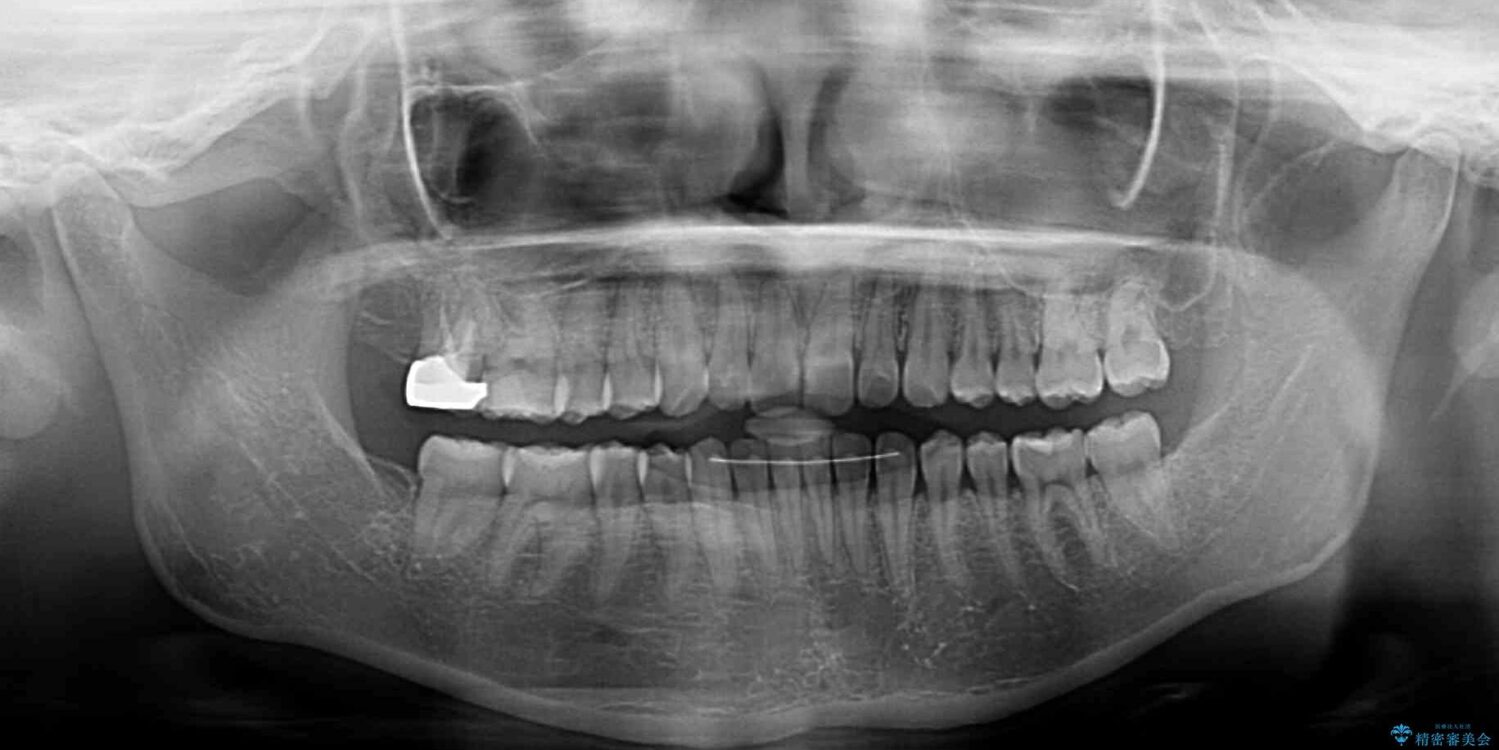

根管治療を行ったままの奥歯と、矯正治療の後戻りを気にして来院された患者様です。

根管治療された歯に症状はなく、オールセラミッククラウンにて補綴治療を行うこととしました。

矯正治療の後戻りは軽微であったため、インビザラインの簡易パッケージであるインビザライン・ライトを用いて歯列を整えることとしました。

クラウンはよりよい咬み合わせで装着したいため、インビザラインを1セット使用して概ね歯列を整えた時点で補綴治療を行い、その後仕上げの矯正治療を行いました。